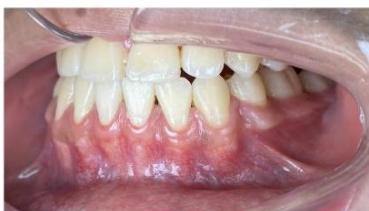

### b) Intraoral Examination

Intraoral examination revealed severe proclination and protrusion of both the maxillary and mandibular incisors [6]. The occlusal relationship was Class I at the canine (tooth 3) and first molar (tooth 6) levels bilaterally. A critical unfavorable biological factor was the proximity of the mandibular incisor roots to the labial cortical plate, representing a high-risk condition when planning extraction-based anterior retraction mechanics [10-12]. All four third molars were present.

Figure 2: Pre-Treatment Intraoral Photographs